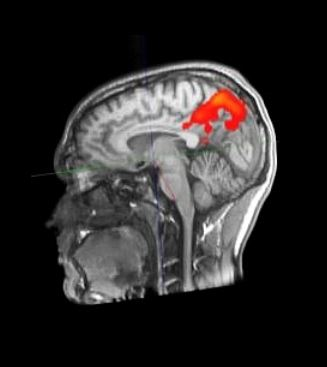

Cu ajutorul noilor metode ale neuroștiinței, abilitățile creierului nostru pot fi examinate din ce în ce mai precis. O privire în interiorul creierului este posibilă cu ajutorul unor metode imagistice precum tomografia computerizată (CT) sau imagistica prin rezonanță magnetică (IRM). Imagistica prin rezonanță magnetică funcțională (fMRI) poate dezvălui modificări ale fluxului sanguin în zonele creierului și, astfel, nu numai structura, ci și activarea. În acest fel, rețeaua neuronală din creier este înregistrată indirect în funcționarea sa. În acest fel, se speră să se înțeleagă mai bine modul în care creierul nostru funcționează și învață. Cu toate acestea, cunoștințele dobândite până în prezent despre modul în care funcționează creierul în timpul învățării sunt foarte limitate din cauza diferitelor limitări metodologice, astfel încât acest subiect rămâne o provocare majoră pentru cercetarea creierului.

fMRT Imaginea unei persoane de 24 de ani - https://de.wikipedia.org/wiki/Funktionelle_Magnetresonanztomographie#/media/Datei:Aktivitaethinten.jpg